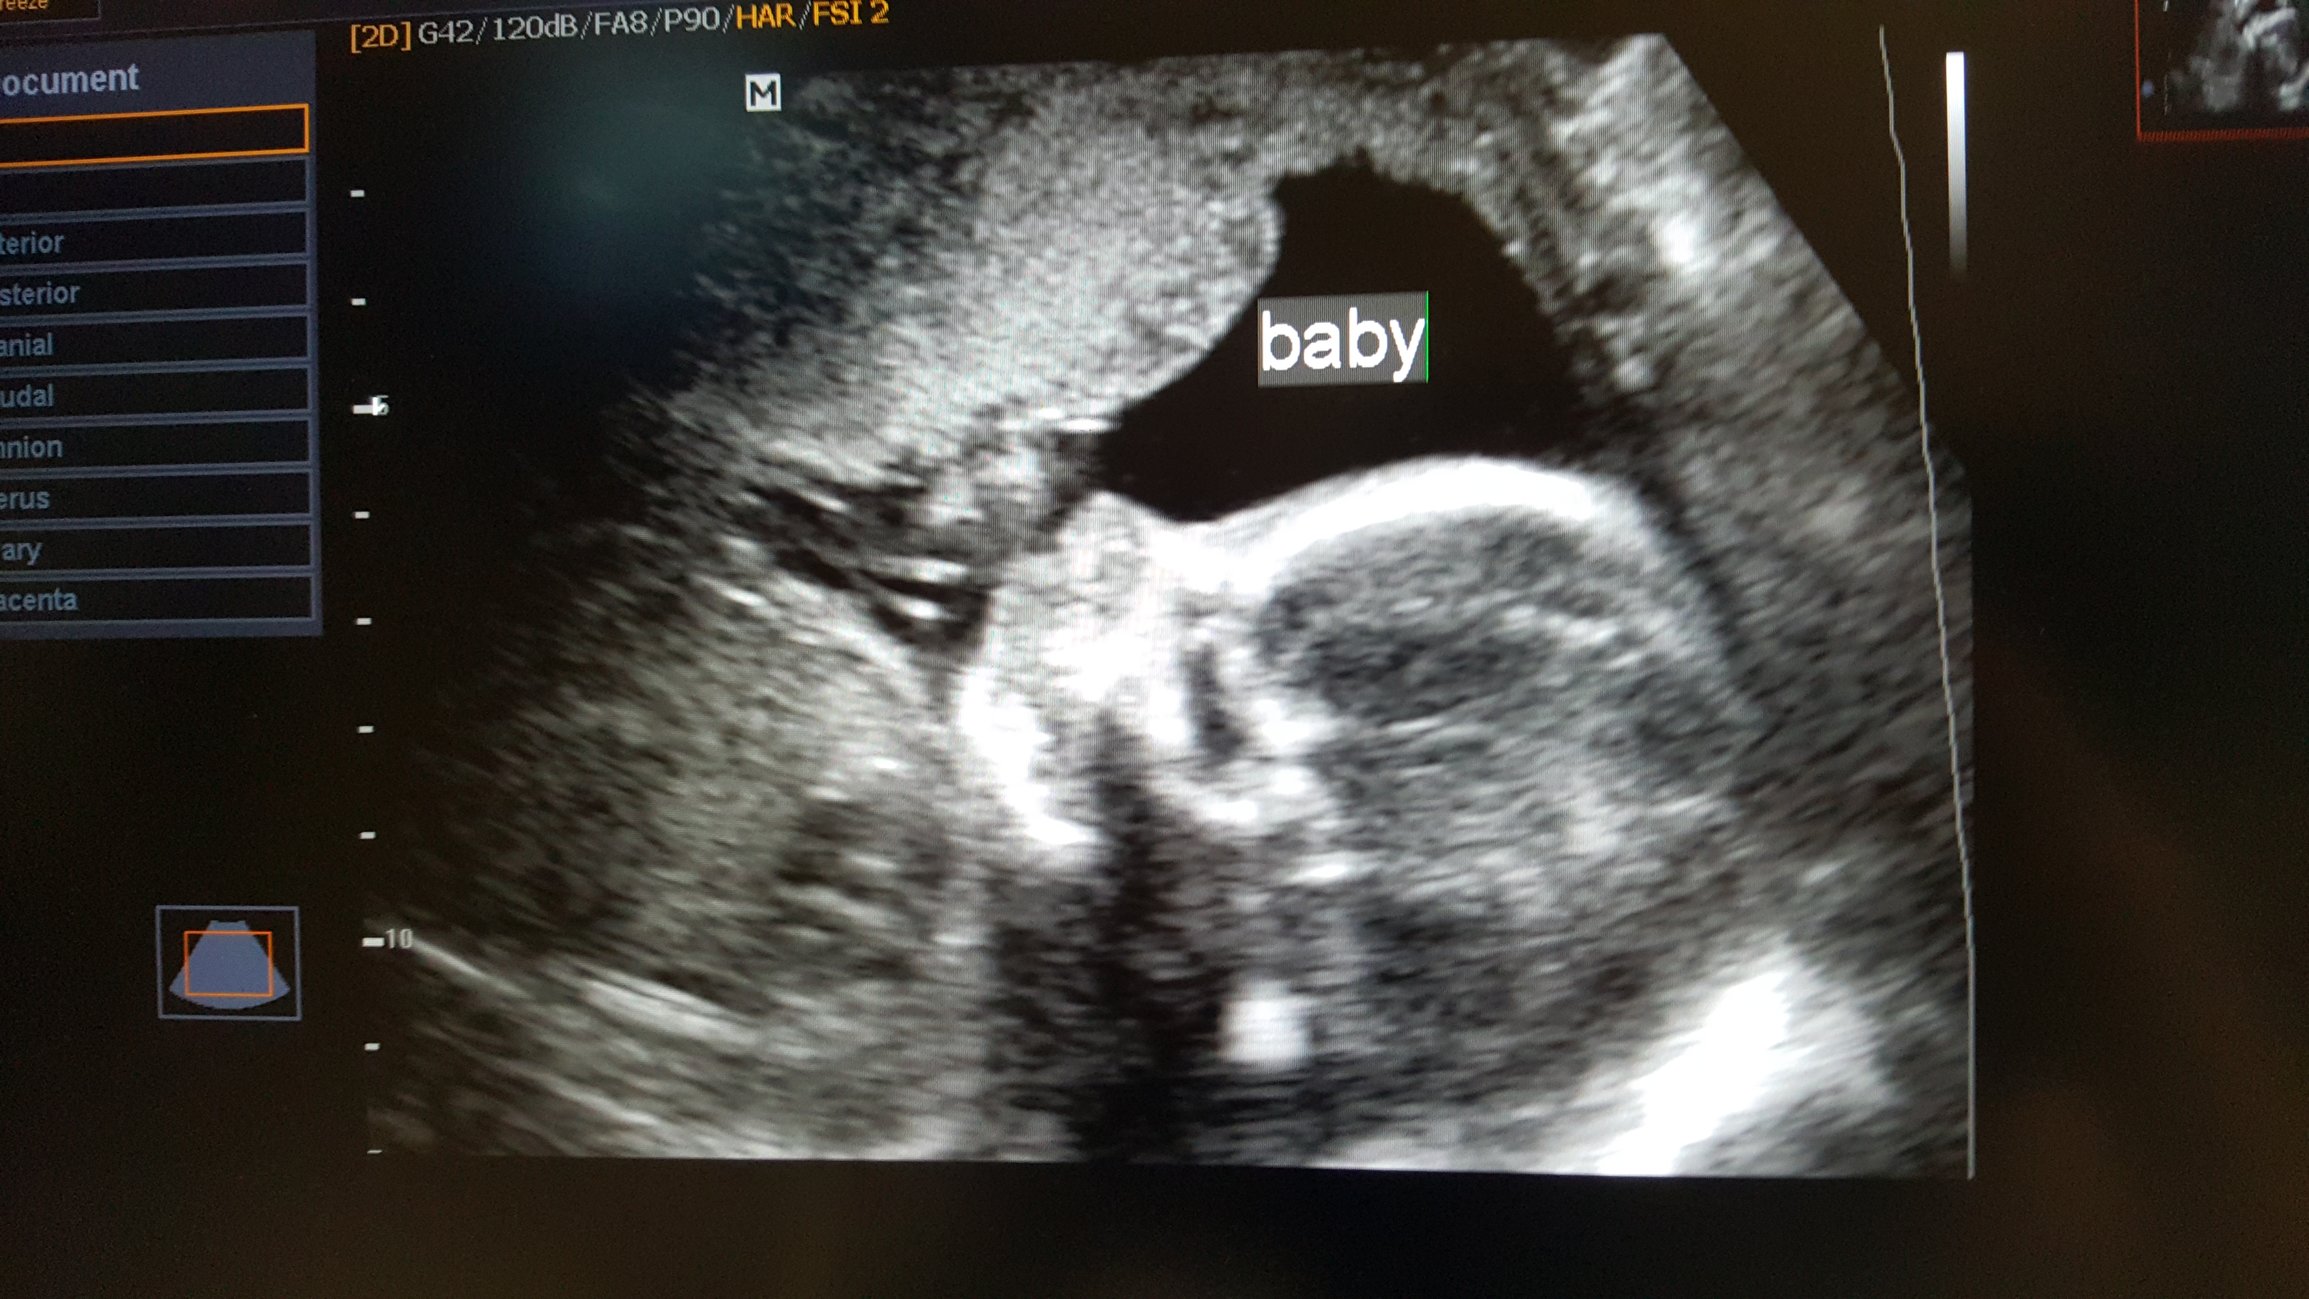

Had my anatomy scan today. She's measuring a little on the small side, 9 oz at 19w 5 d, which they said is in the 12th percentile, but otherwise she's doing great!